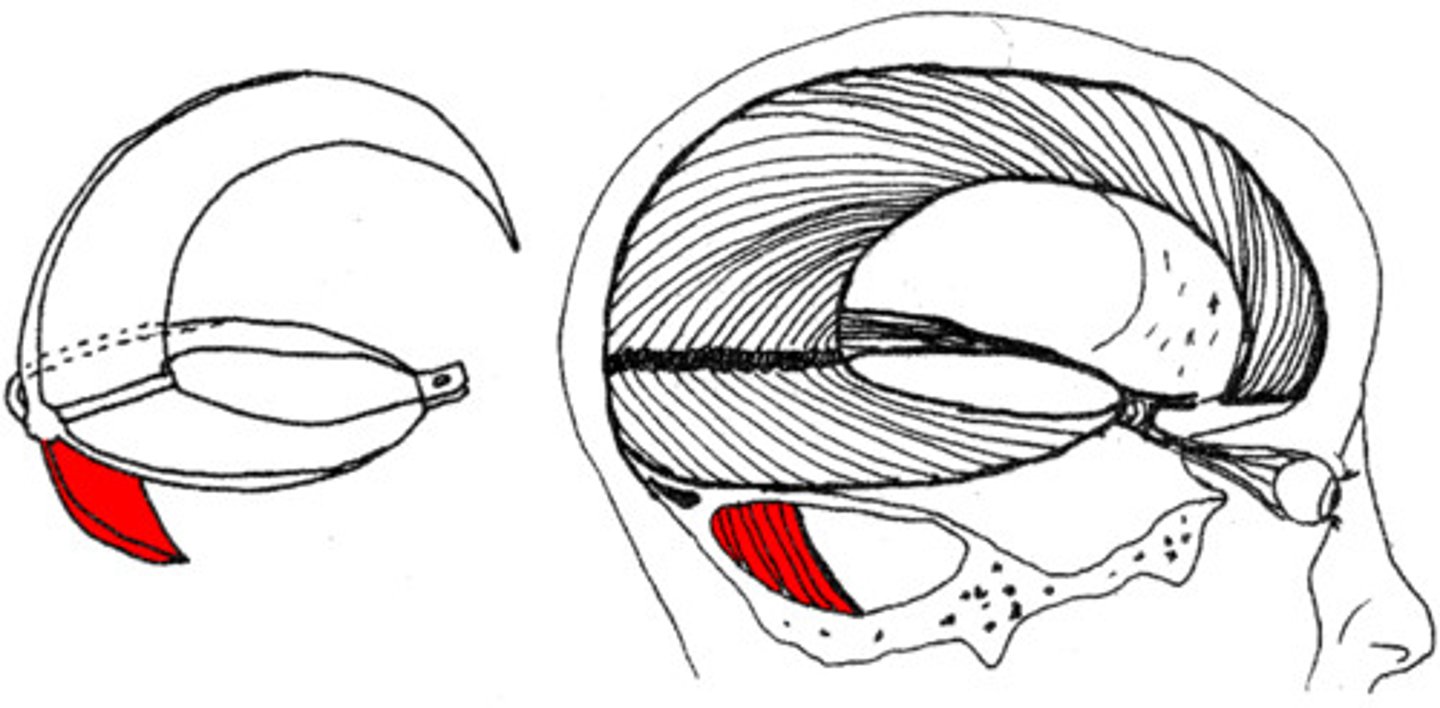

dural folds

Folded inner layer of dura mater

Extend into cranial cavity

Stabilize and support brain

falx cerebri

separates the two hemispheres of the cerebrum

tentorium cerebelli

horizontal dural fold over cerebellum and in transverse fissure

falx cerebelli

separates the two hemispheres of the cerebellum